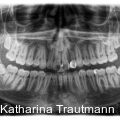

Die interdisziplinäre Zusammenarbeit spielt in der modernen Kieferorthopädie eine zentrale Rolle, insbesondere bei komplexeren Behandlungsfällen, die über das alltägliche Behandlungsspektrum hinausreichen. Fotos: © Dr. Johanna Katharina Trautmann